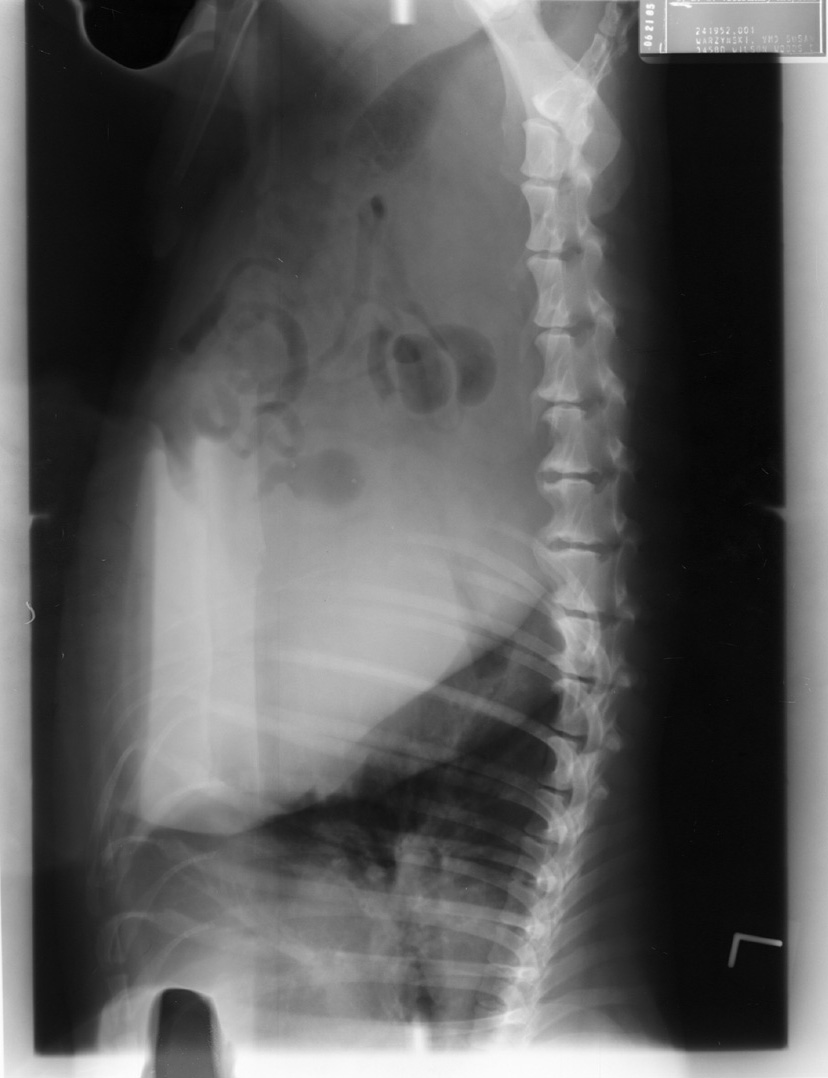

Overlapping of Film, Automatic Processing

Overlapping of two films in automatic processor. Note artifact along one long edge of each film.